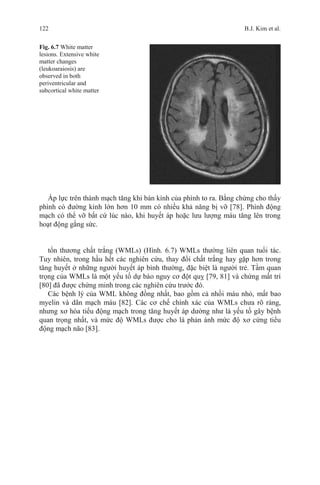

Working Party. Br Med J (Clin Res).1985;291:97–104.

22. The IPPPSH Collaborative Group. Cardiovascular risk and risk factors in a randomised trial of

treatment based on the beta-blocker oxprenolol: The International Prospective Primary